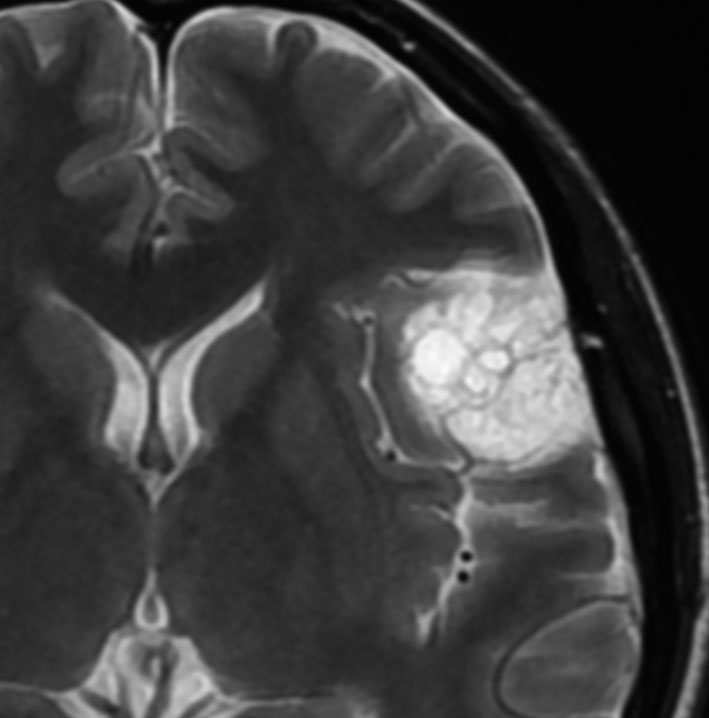

angiomatous meningioma WHO grade 1 血管腫様髄膜腫

術前検査ではまるで膠芽腫のような画像です。でも,開けてみれば髄膜腫ということはすぐにわかる肉眼所見です。硬膜の至る所から腫瘍血管が流入して出血性腫瘍です。

多数の小血管から構成される組織像です。右のvimentin染色は陽性です。

核小体明瞭な大小不同な類円形核からなる細胞境界が不明瞭な腫瘍細胞がみられ,ヘモジデリン貪食マクロファージも認められます。MIB-1染色率は2-3%でグレード1です。